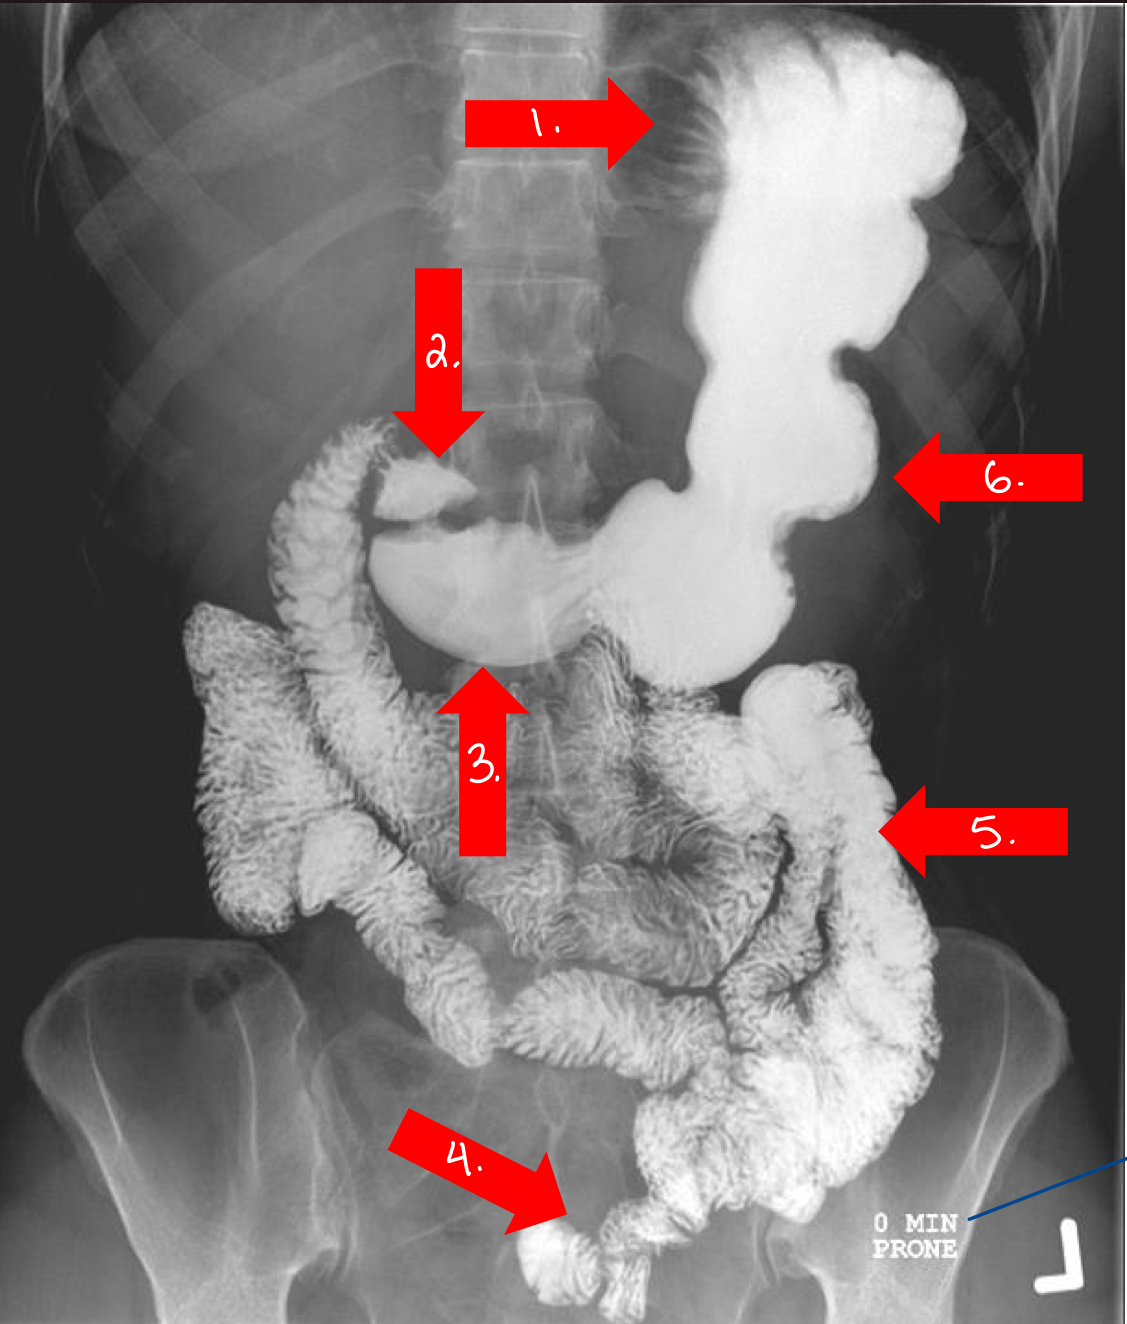

What is A

(arrow may be misleading — what is the organ)

small intestine

What is B

plica

What is C

plicae circulares

What is D

villi